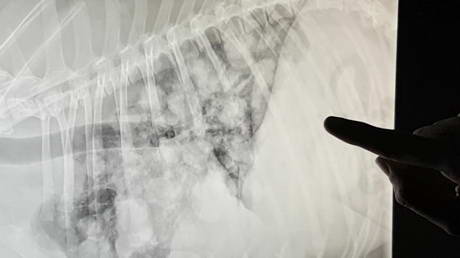

Breathing Issues!

Play this video

29 Jan 2017

(Duration 01:53)